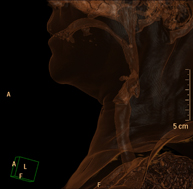

Prova radiològica que consisteix en obtenir imatges del coll d'alta definició anatòmica, mitjançant l'ús d'un equip de TC (Tomografia Computeritzada). Indicacions: estudi de la tiroide, control de tumors tractats, estudi de ganglis, infeccions i abscessos. - TC Laringe

Prova radiològica que consisteix en obtenir imatges de la laringe d'alta definició anatòmica, mitjançant l'ús d'un equip de TC (Tomografia Computeritzada). Indicacions: afonia sobtada o crònica, dificultat respiratòria. - TC Òrbites